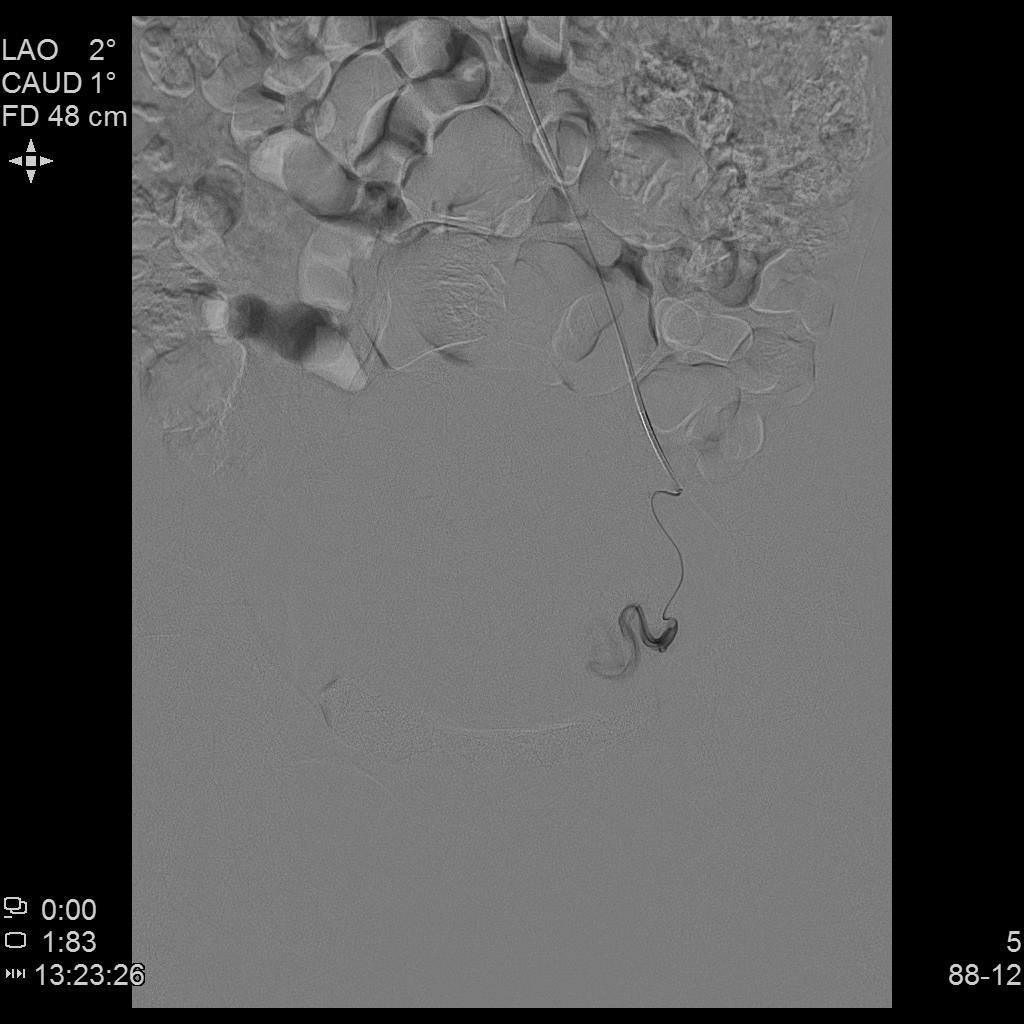

左侧子宫造影

右侧子宫动脉造影